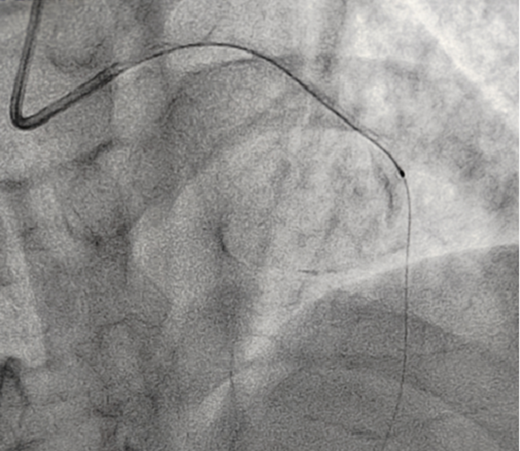

OCT檢測是將一條頭端帶光學(xué)透鏡的成像導(dǎo)管放在冠脈血管里,通過高速旋轉(zhuǎn)回撤,不到3秒鐘就可以幫我們診斷清楚血管里面的結(jié)構(gòu)和斑塊性質(zhì),就像直接把眼睛放進血管里看一樣,整個診斷過程非常安全可靠。

經(jīng)OCT檢查結(jié)果顯示:前降支中段鈣化,內(nèi)膜光滑,最小管腔面積僅為1.19 mm2。近段斑塊破裂,可見血栓影,最小面積為2.63mm2??蛇x擇先進行抗栓治療,擇期處理冠脈病變。這讓張先生懸著的一顆心終于放下來。